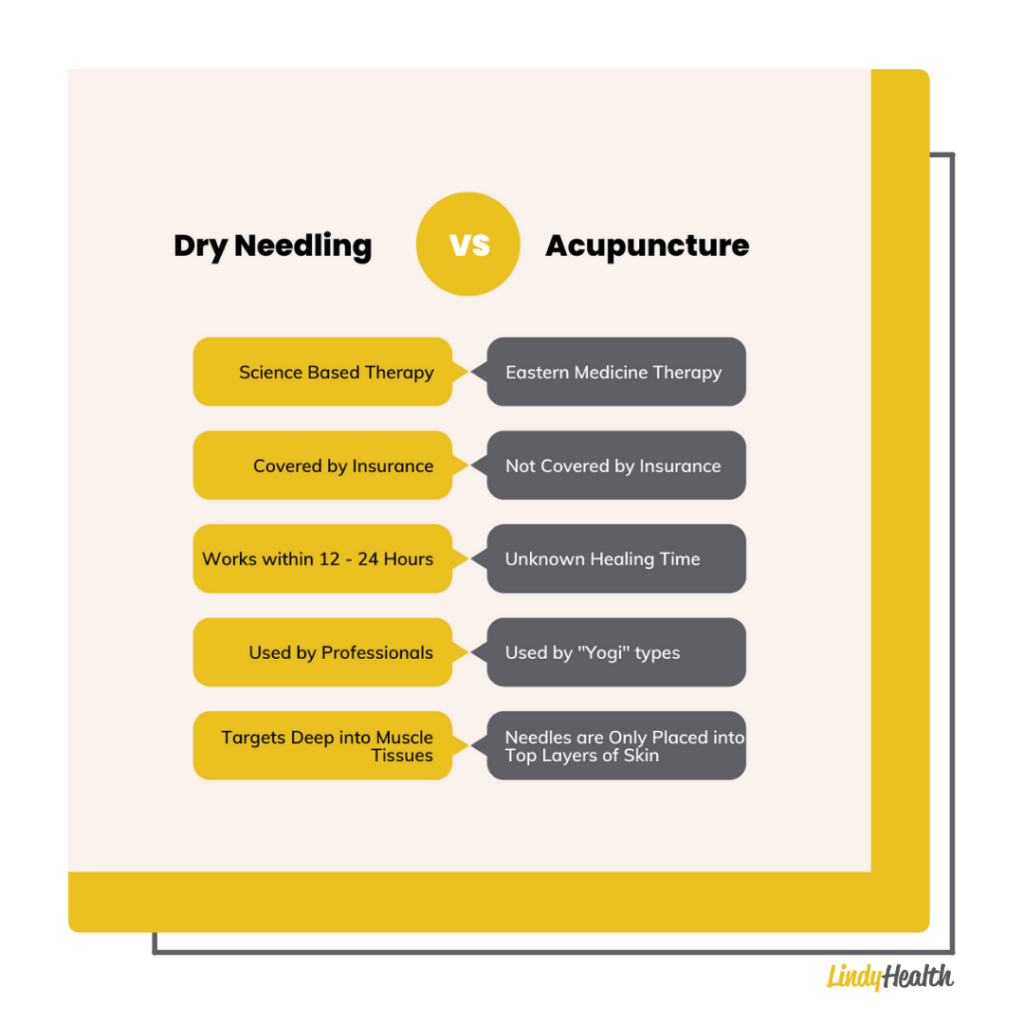

Dry Needling vs Acupuncture: Pros and Cons | Lindy Health

What is dry needling? Isn’t it just acupuncture? – Jade Acupuncture and …

Dry needling – Isn’t that like acupuncture?